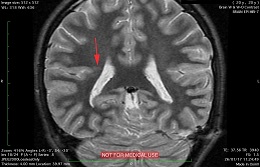

This recent MRI exam WITHOUT Contrast in IHC, revealed a subtle congenital malformation of cortical development within right parietal lobe.

A subtle linear band intensity extending between deep posterosuperior aspect of right Sylvian fissure and posterior aspect of corpus of right lateral ventricle (isointense with gray matter on all sequences). These MRI findings strongly suggest "Type II (Taylor type) focal cortical dysplasia (transmantle cortical dysplasia)" or "transmantle gray matter heterotopia". Virtually, they may be representing two different names for the same entity.